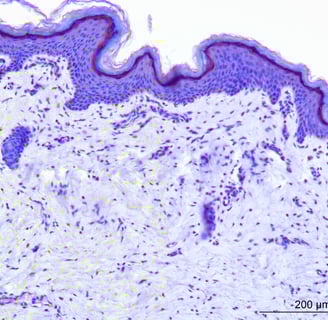

Safety of any product on the skin is extremely important. But everyone is different. Some skin is resistant and some highly sensitive. Products need to be checked for different populations and different areas of the human body.